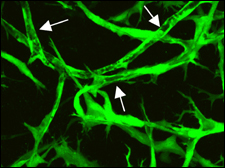

Until now, laboratory-grown blood vessels didn’t last very long, not long enough to use for replacements that must last a lifetime. To solve the problem, a Jain team, led by Naoto Koike, a research fellow at Mass General, mixed human cells from the lining and muscular outer coating of umbilical cord veins. The combo was nurtured in culture for about a day, then Koike and his crew transferred the cells to the brains of mice where they started to form long, branching tubes.

“The implants survived, grew, and connected beautifully with the mice’s own system of blood vessels,” Jain explains. “These networks have lasted for a year, about half the lifetime of a mouse.”